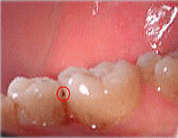

口の中を検査したら歯と歯の

間に虫歯が見つかりました

レントゲンでは虫歯が見当たりません。

当然、削る必要はありません。